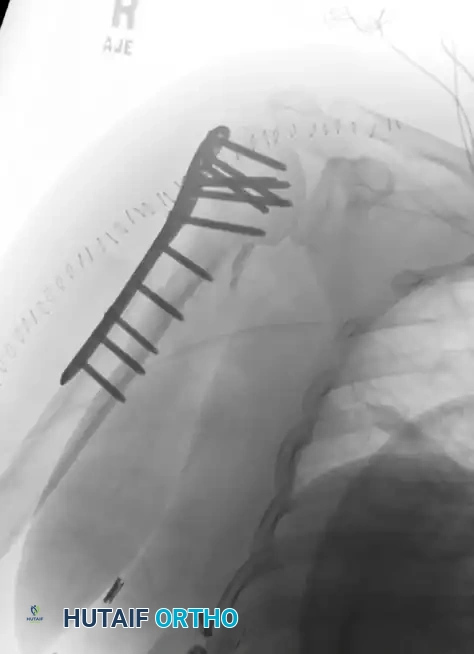

التثبيت الداخلي بالشرائح والمسامير المغلقة

تُعد عملية الرد المفتوح والتثبيت الداخلي باستخدام الشرائح المعدنية ذات المسامير المغلقة هي المعيار الذهبي لعلاج الكسور المعقدة والمتعددة الأجزاء. تعمل هذه الشرائح كدعامة قوية بزوايا ثابتة، مما يوفر صلابة استثنائية حتى في حالات هشاشة العظام.

يتم إجراء العملية من خلال شق جراحي أمامي في الكتف، حيث يقوم الجراح بإعادة ترتيب العظام المكسورة بدقة متناهية، ثم يثبتها باستخدام الشريحة والمسامير. غالباً ما يتم إضافة خيوط متينة لربط الأوتار بالشريحة لضمان أقصى درجات الثبات.

إليك بعض الصور الإشعاعية والرسوم التوضيحية الإضافية التي توضح أشكال التثبيت الجراحي المختلفة لكسور أعلى عظمة العضد